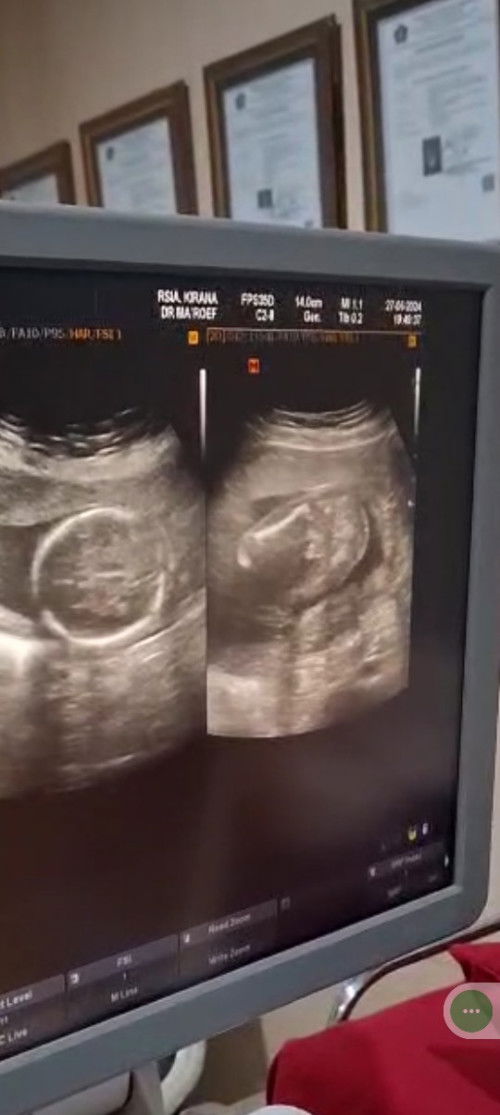

Ada yang tau ini jenis kelamin apa bund? Dokter gak mau ngasih tau soalnya, katanya biar tau sendiri

cowok kyknya bun, aku anak pertama cewek ga ada tonjolan kyk gitu soalnya disela² paha 😂

kalau diliat sih itu kayak ada monasnya bun, kayaknya laki laki

iyaa bund . kalo menurutku juga itu monasnya hehe

cowok bun kayanya